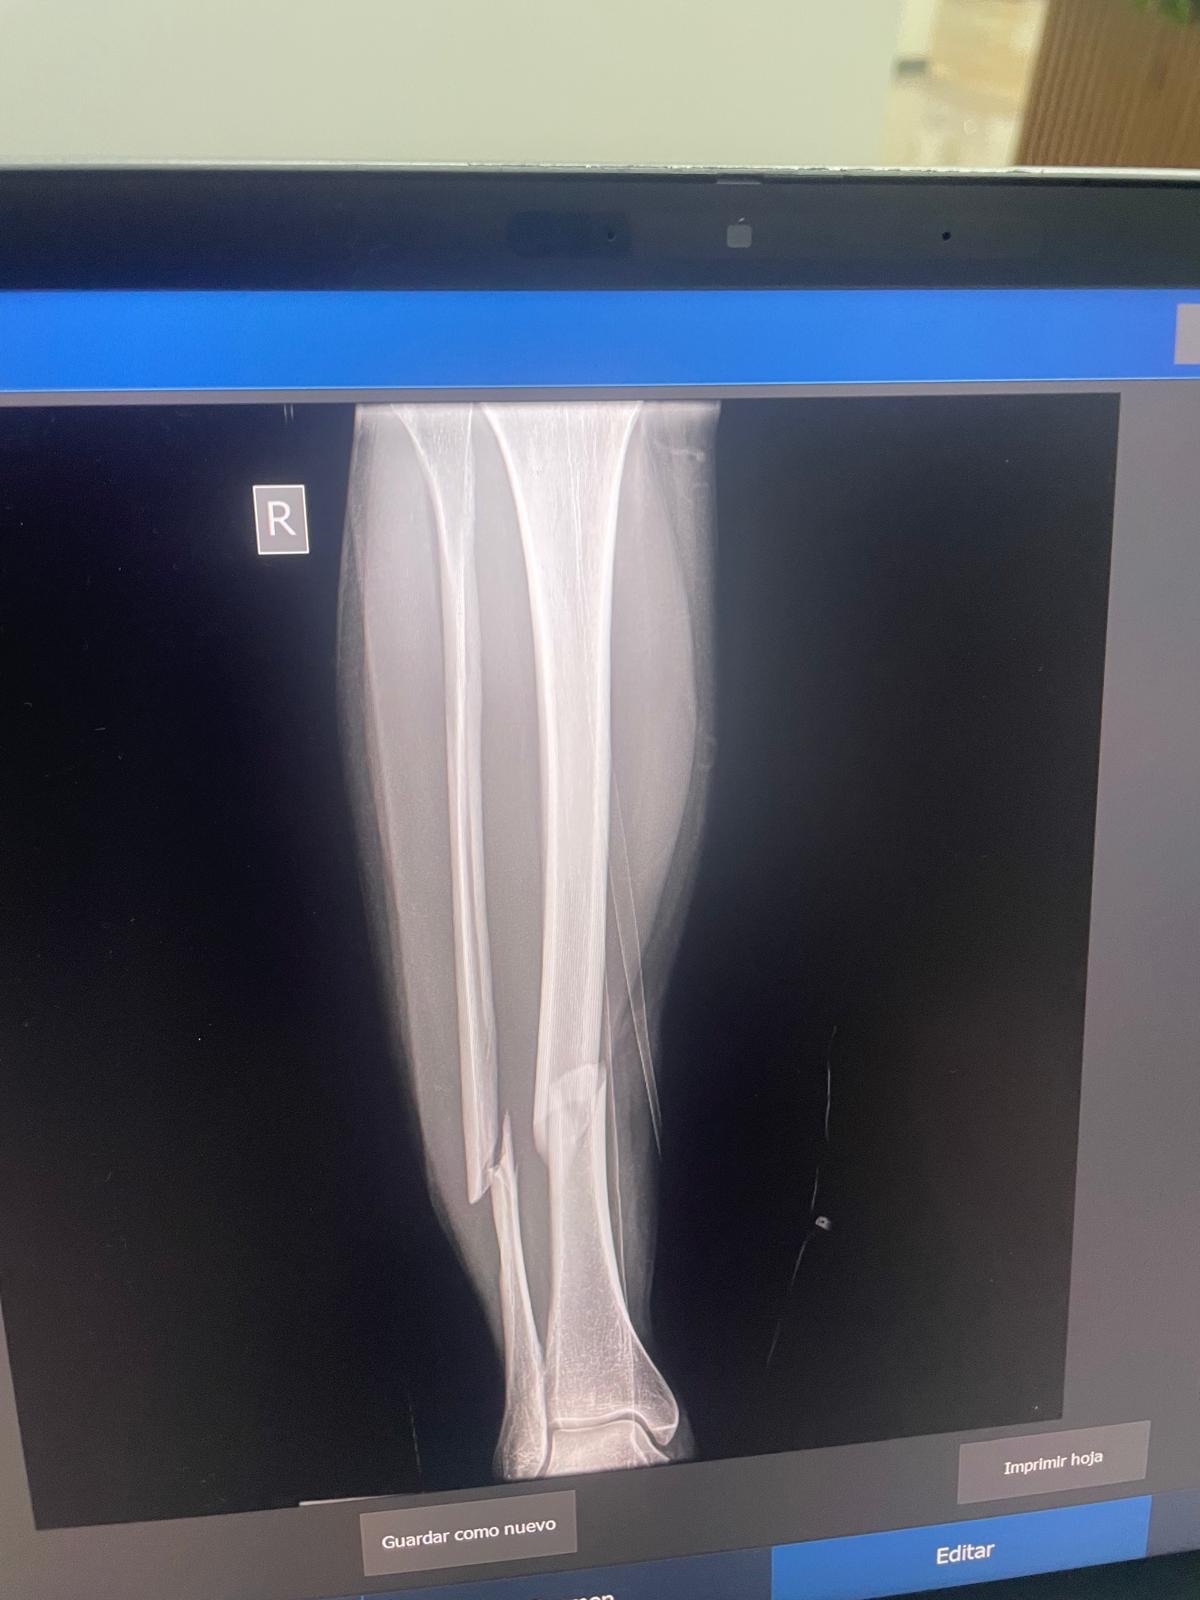

We’re so relieved and grateful to share that Malin’s surgery went well and she’s now beginning the healing process. The procedure was successful, and she’s currently resting and recovering.

While this is a major step forward, Malin still needs help covering the full cost of the surgery, hospital stay, and the months of recovery ahead. She’ll also need physical therapy multiple times a week, which is essential for her to fully regain strength and mobility in her leg.